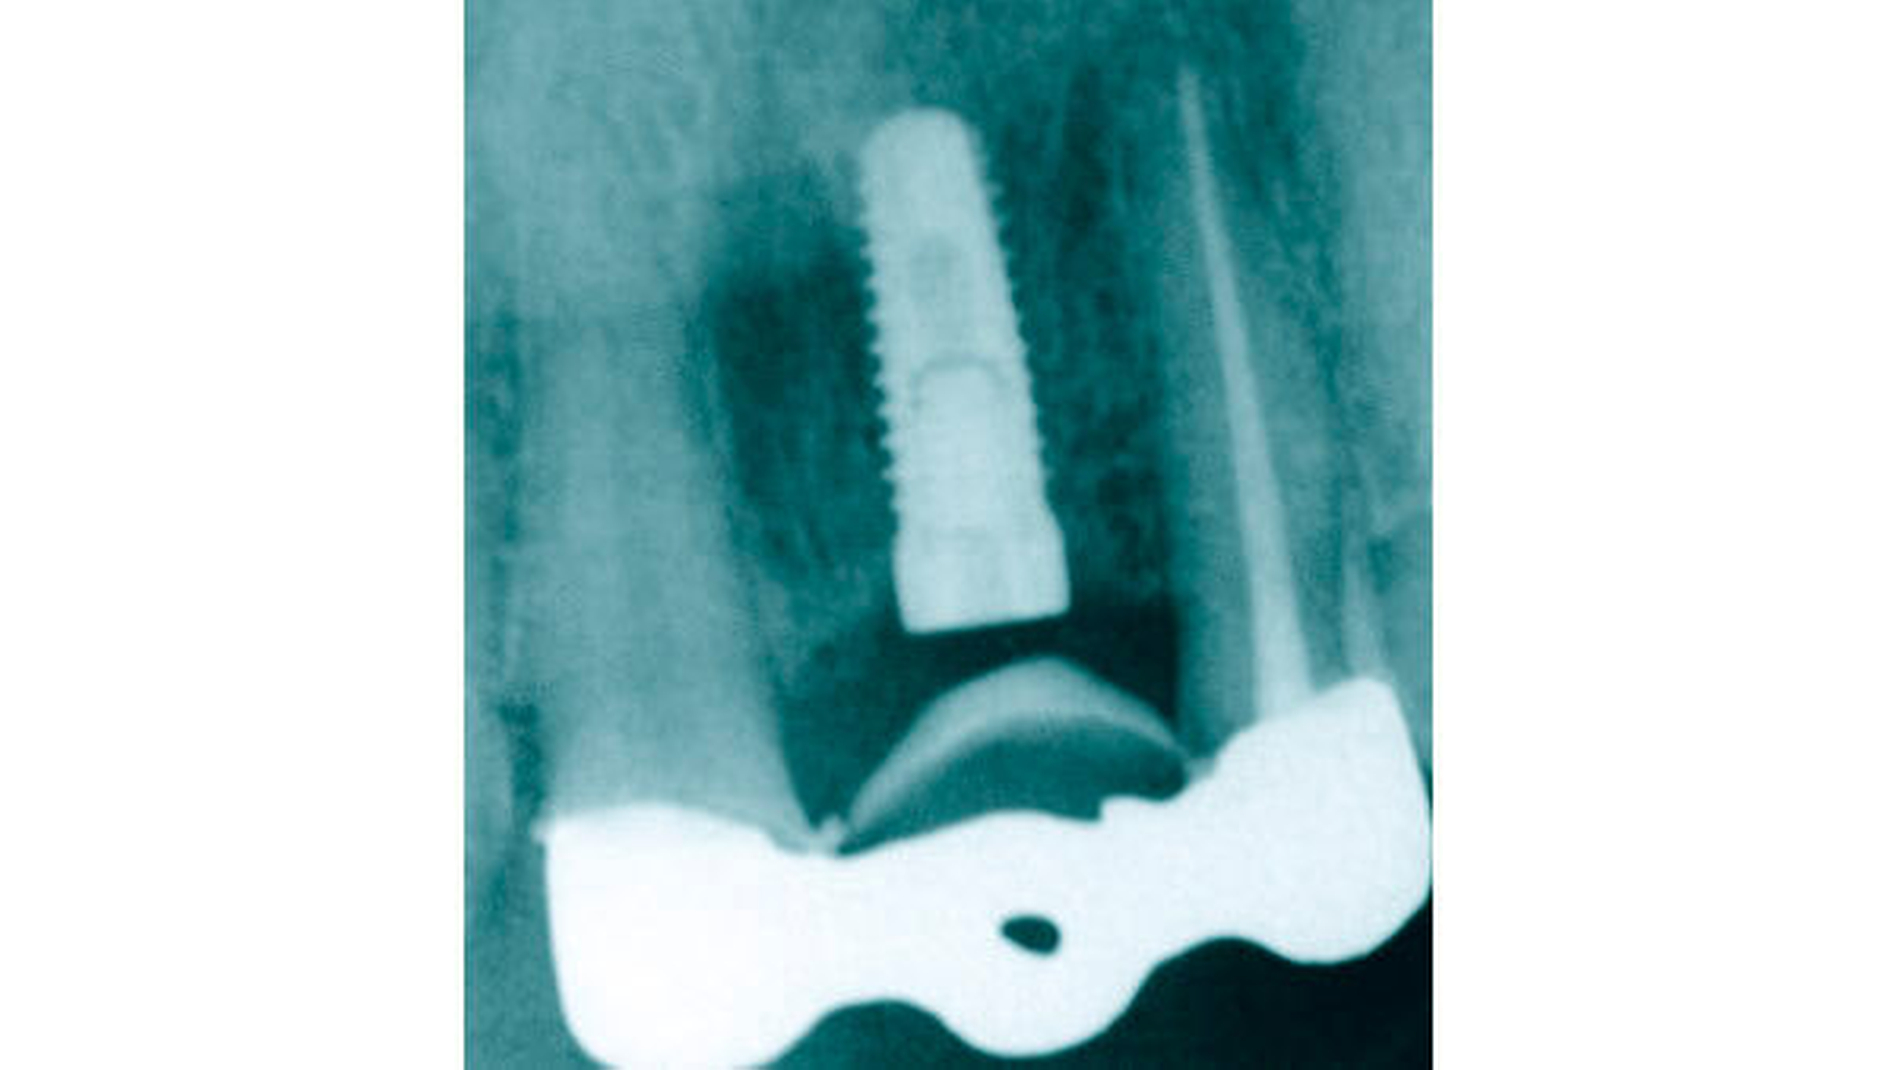

Nach forcierter Extrusion (Abbildung 9) mit vier Gummiwechseln innerhalb von acht Tagen und einer ersten Stabilisierungsphase zeigten sich im Röntgenbild (Abbildung 10) erste, deutliche Reossifkationen.

Nach etwa zehn Monaten wurde noch einmal ein Extrusionsimpuls mit zweimaligem Gummiwechsel gesetzt. Etwa zwei Monate später zeigte sich radiologisch ausreichend Knochen bei gleichzeitig taktiler Stabilität (Lockerungsgrad 0), um den Zahn doch erhalten zu können. Die Sondierungstiefen lagen mesial und distal nur noch bei maximal 5 mm, und die ursprünglich durchgängige Furkation lies sich nicht mehr sondieren.

Die Wurzelfüllung wurde suffizient revidiert (Abbildung 11) sowie ein Deep Scaling von 37 bis 35 durchgeführt. Aufgrund der nunmehr guten Prognose wurde im Rahmen einer Gesamtsanierung auch der Zahn 36 mit einer Lithiumdisilikatkrone (Emax, Fa. Ivoclar Vivadent) neu versorgt (Abbildung 12).

Sowohl die klinische Situation nach Eingliederung als auch die radiologische Nachkontrolle zeigen einen suffizient versorgten eigenen Zahn 36. Dies konnte trotz der ursprünglichen Osteolyse von etwa 80 Prozent ohne Zuhilfenahme von Fremdmaterialien und ohne jegliche chirurgische Intervention erreicht werden.

Ergebnis: Der a priori extraktionswürdige Zahn 36 konnte durch die Anwendung der forcierten Extrusionstherapie völlig noninvasiv langfristig erhalten werden. Ein Jahr nach Eingliederung ist der Zahn parodontal stabil mit Messwerten unter 3 mm bei Sechspunktmessung. Die Gingiva ist zartrosa und volumenstabil.